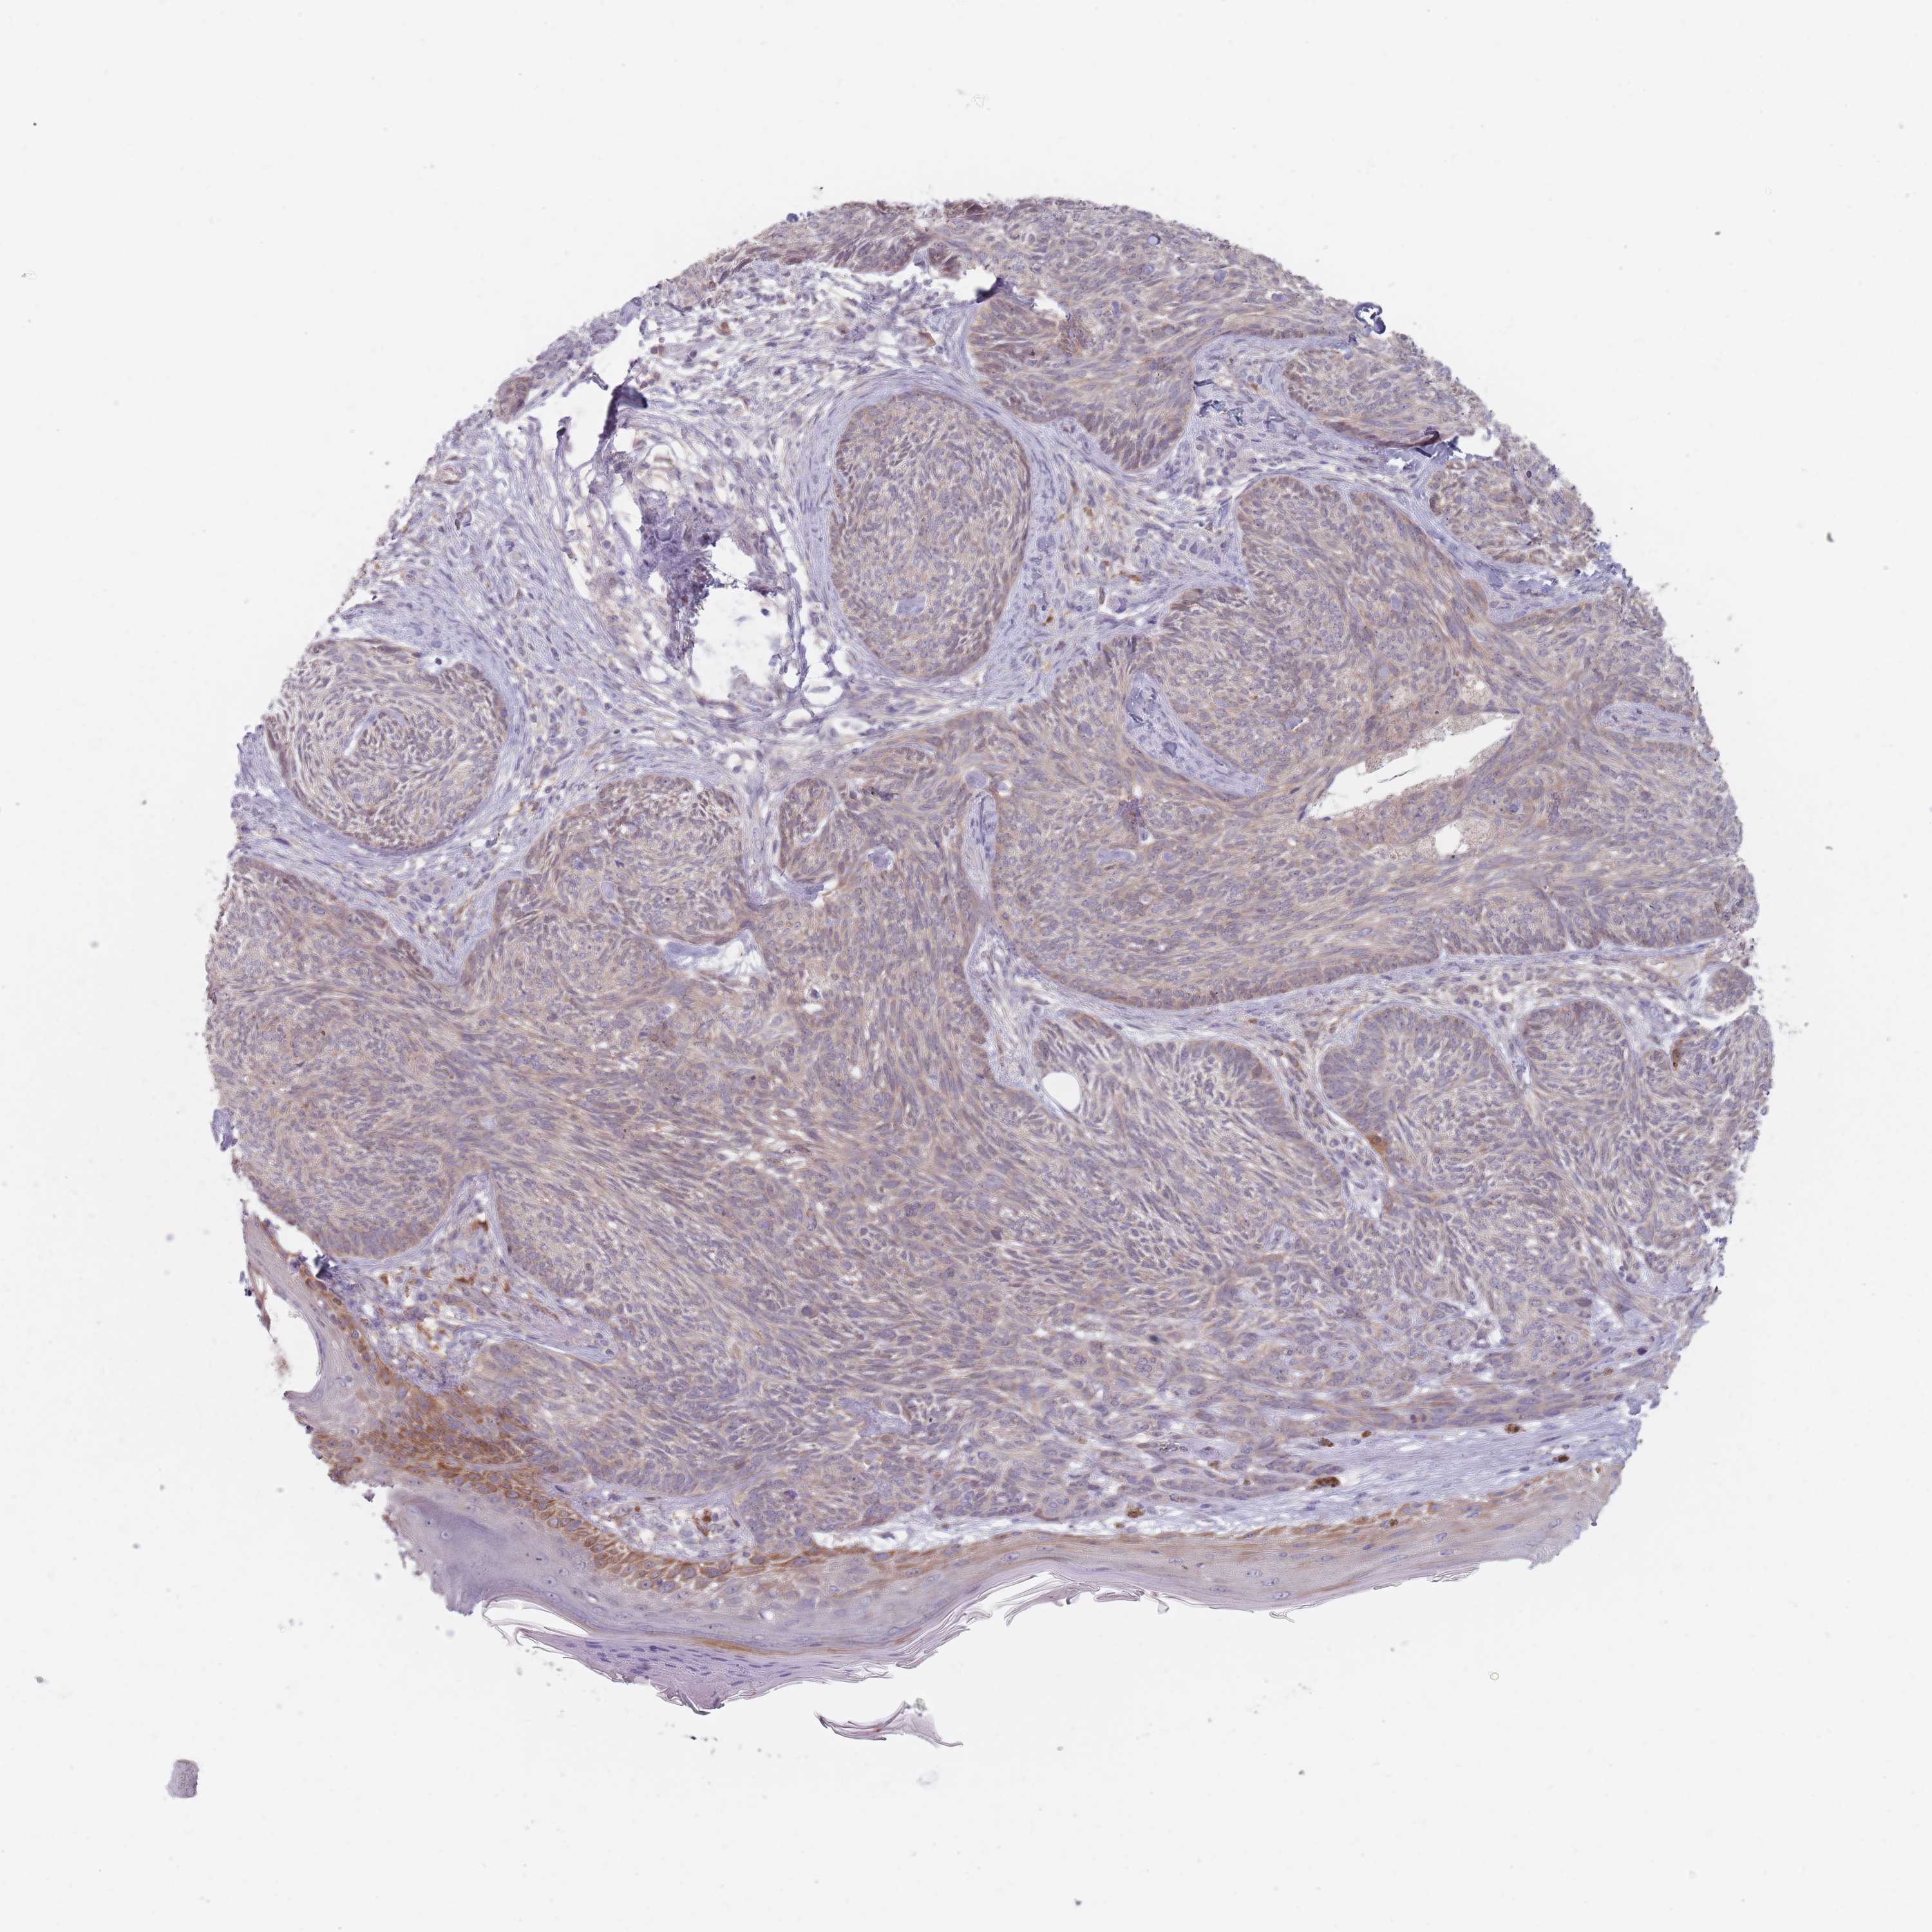

Basal cell and squamous cell cancer

SKIN CANCER - Protein expressioni

A mouse-over function shows sample information and annotation data. Click on an image to view it in a full screen mode. Samples can be filtered based on level of antibody staining by selecting one or several of the following categories: high, medium, low and not detected. The assay and annotation is described here.

Each image is clickable and will lead to virtual microscopy that enables deeper exploration of all samples and also displays staining intensity scores, fraction scores and subcellular localization as well as patient and tissue information for each sample.

Antibody HPA048164

Squamous cell carcinoma, NOS

Squamous cell carcinoma, metastatic, NOS